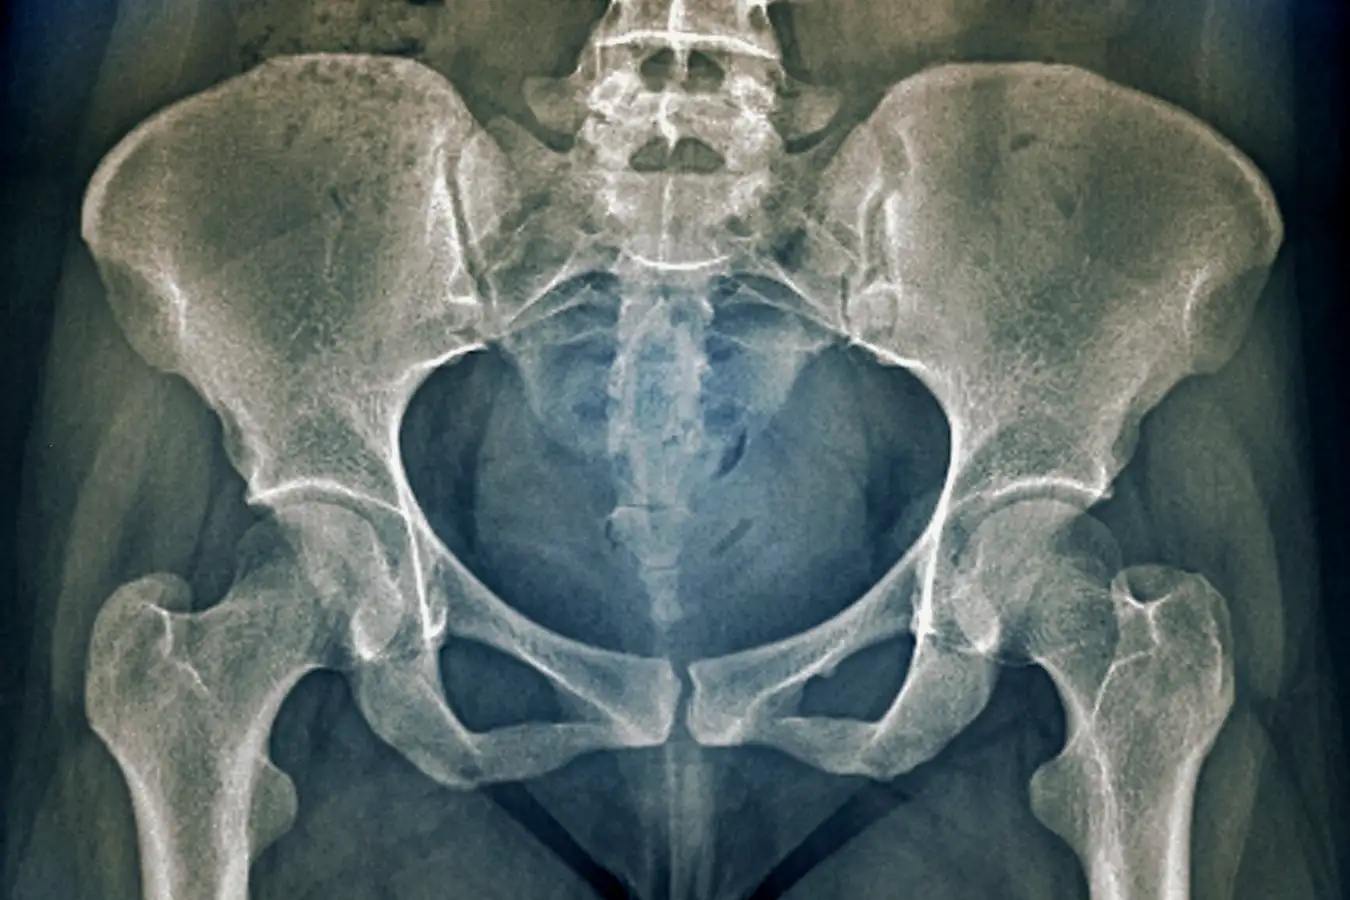

Research shows that the female pelvis in some countries has narrowed by more than 4 cm in the past century

ZEPHYR/SCIENCE PHOTO LIBRARY